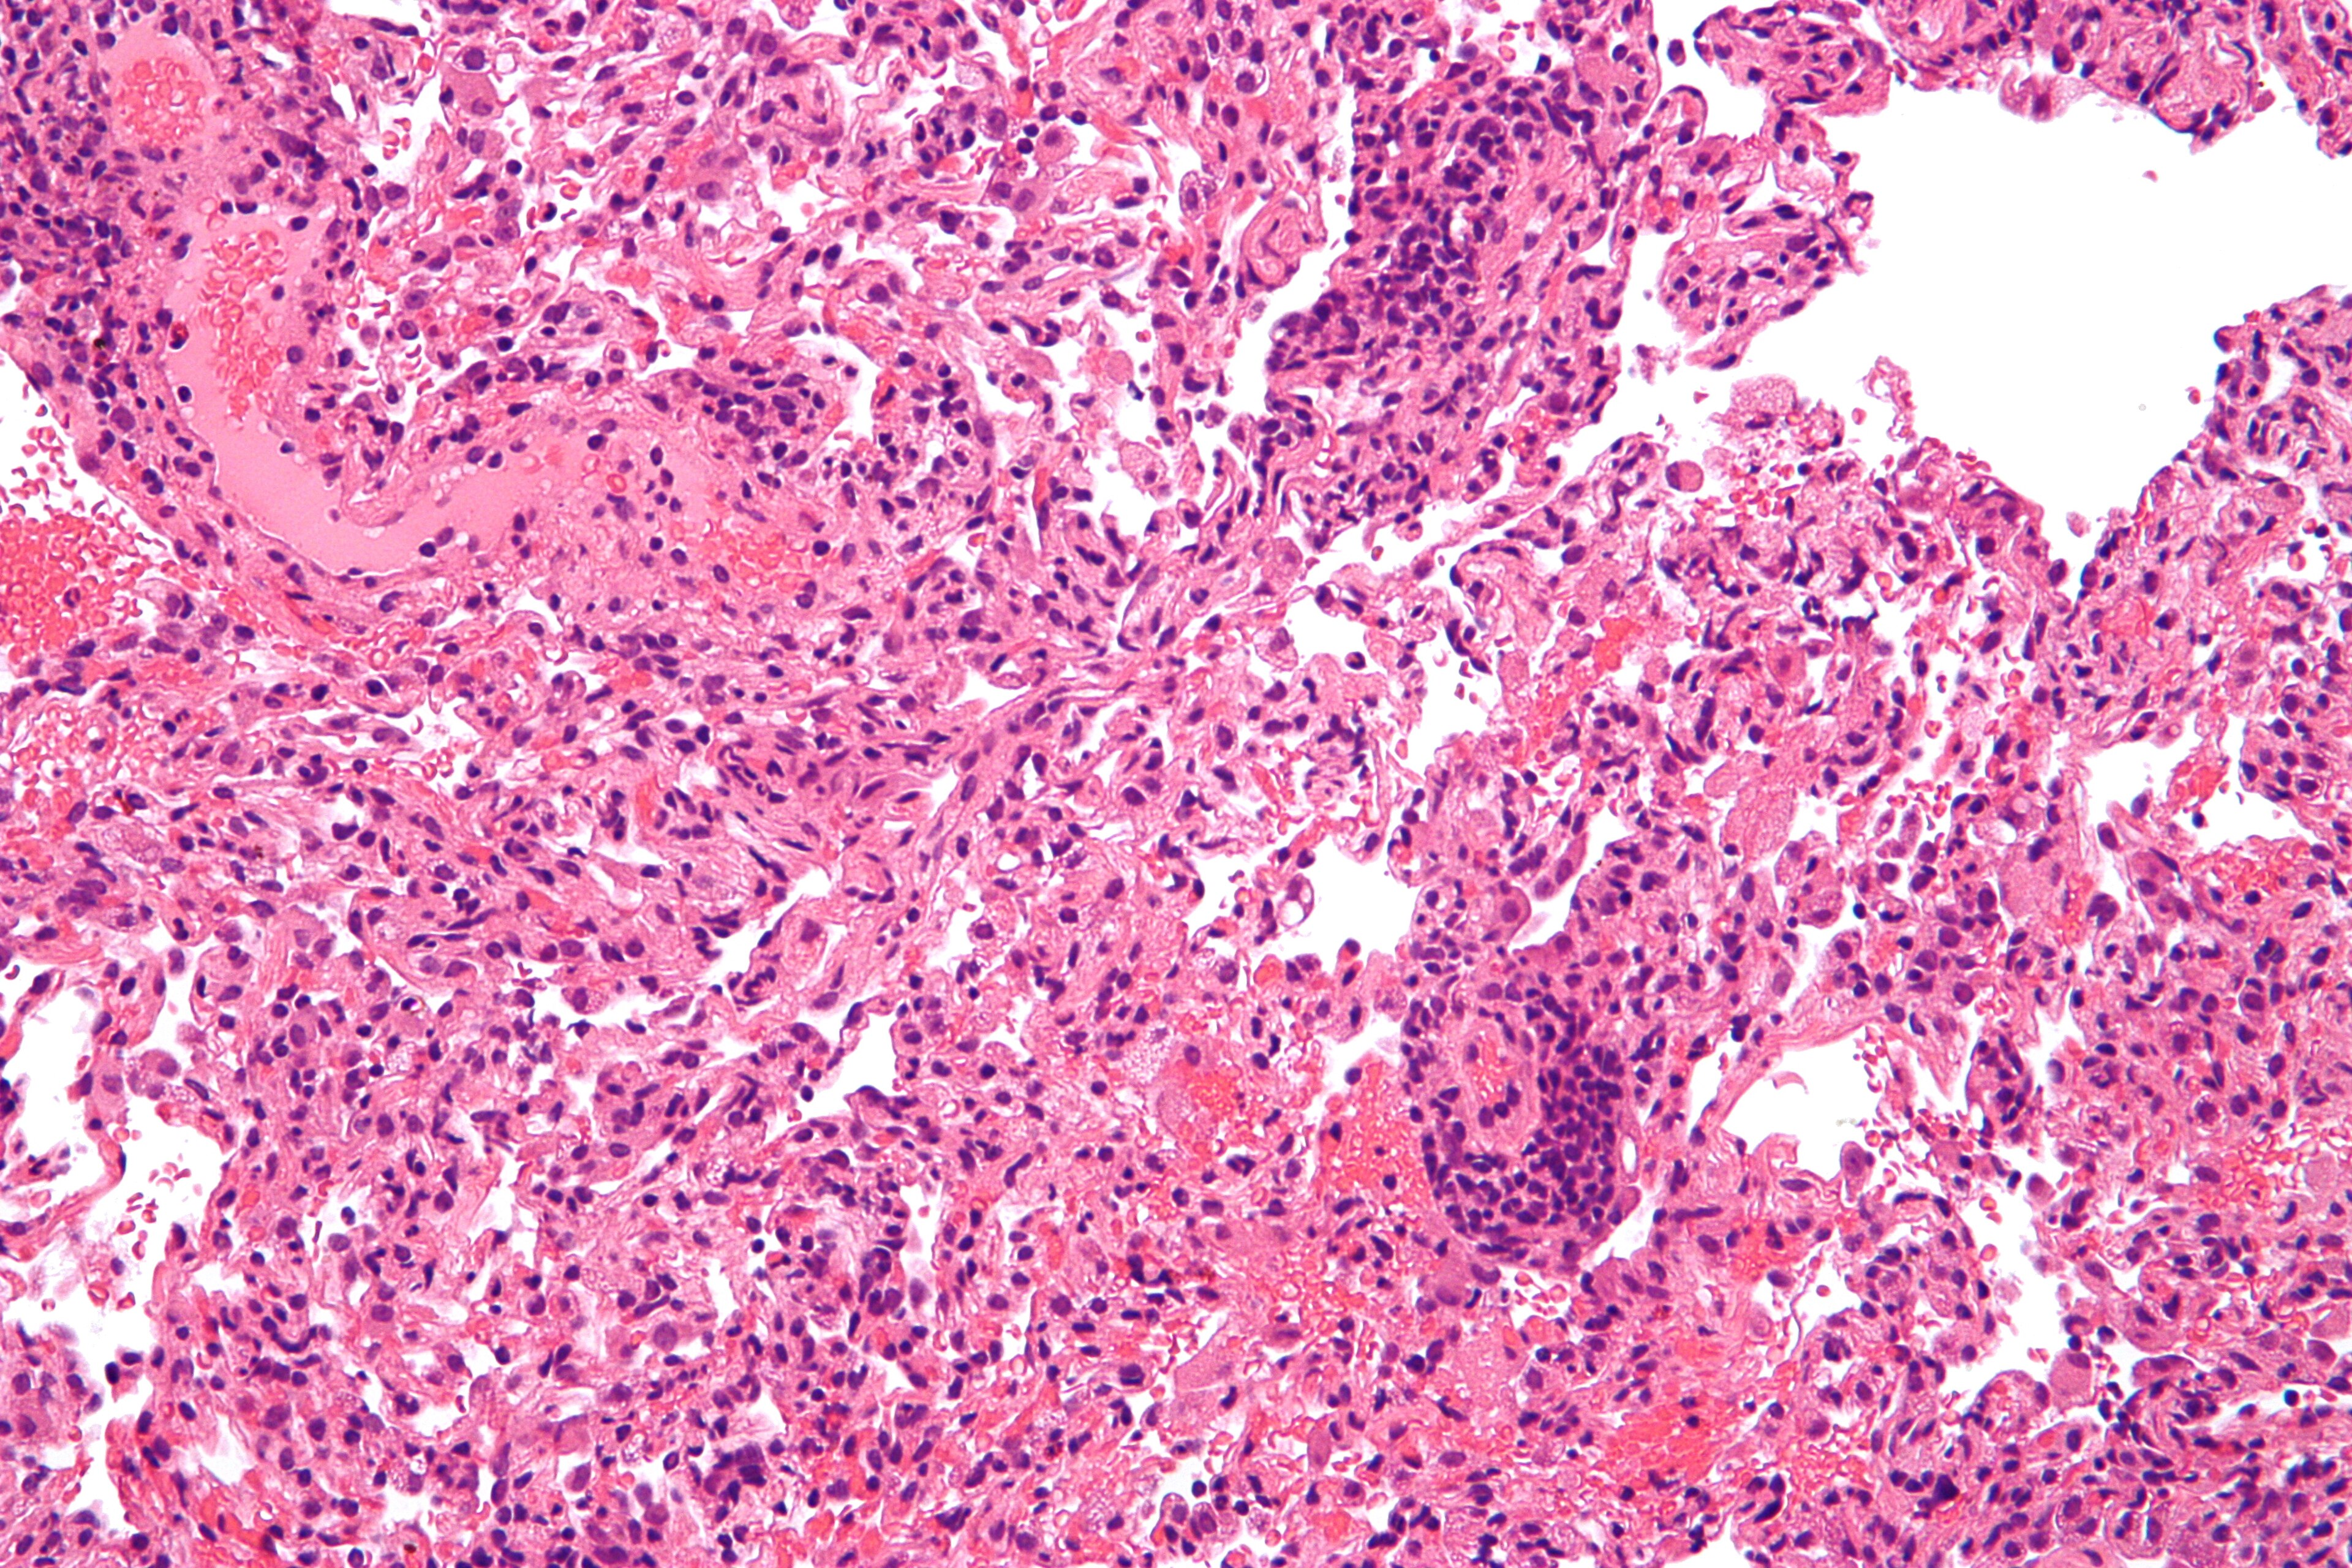

| Mikrograf yang menunjukkan penolakan transplantasi paru-paru |

Penolakan transplantasi terjadi ketika jaringan yang ditransplantasi ditolak oleh sistem imun penerimanya, sehingga jaringan yang ditransplantasi pun rusak. Penolakan transplantasi dapat dikurangi dengan menentukan kemiripan molekuler antara penyumbang dan penerima, serta dengan menggunakan obat imunosupresif seusai transplantasi.[1]

Penolakan ini sendiri merupakan respons imun adaptif (melalui perantara sel T pembunuh yang memicu apoptosis pada sel sasaran) serta imunitas humoral (melalui perantara sel B teraktivasi yang mengeluarkan molekul-molekul antibodi), walaupun terdapat juga komponen respons imun bawaan (fagosit).